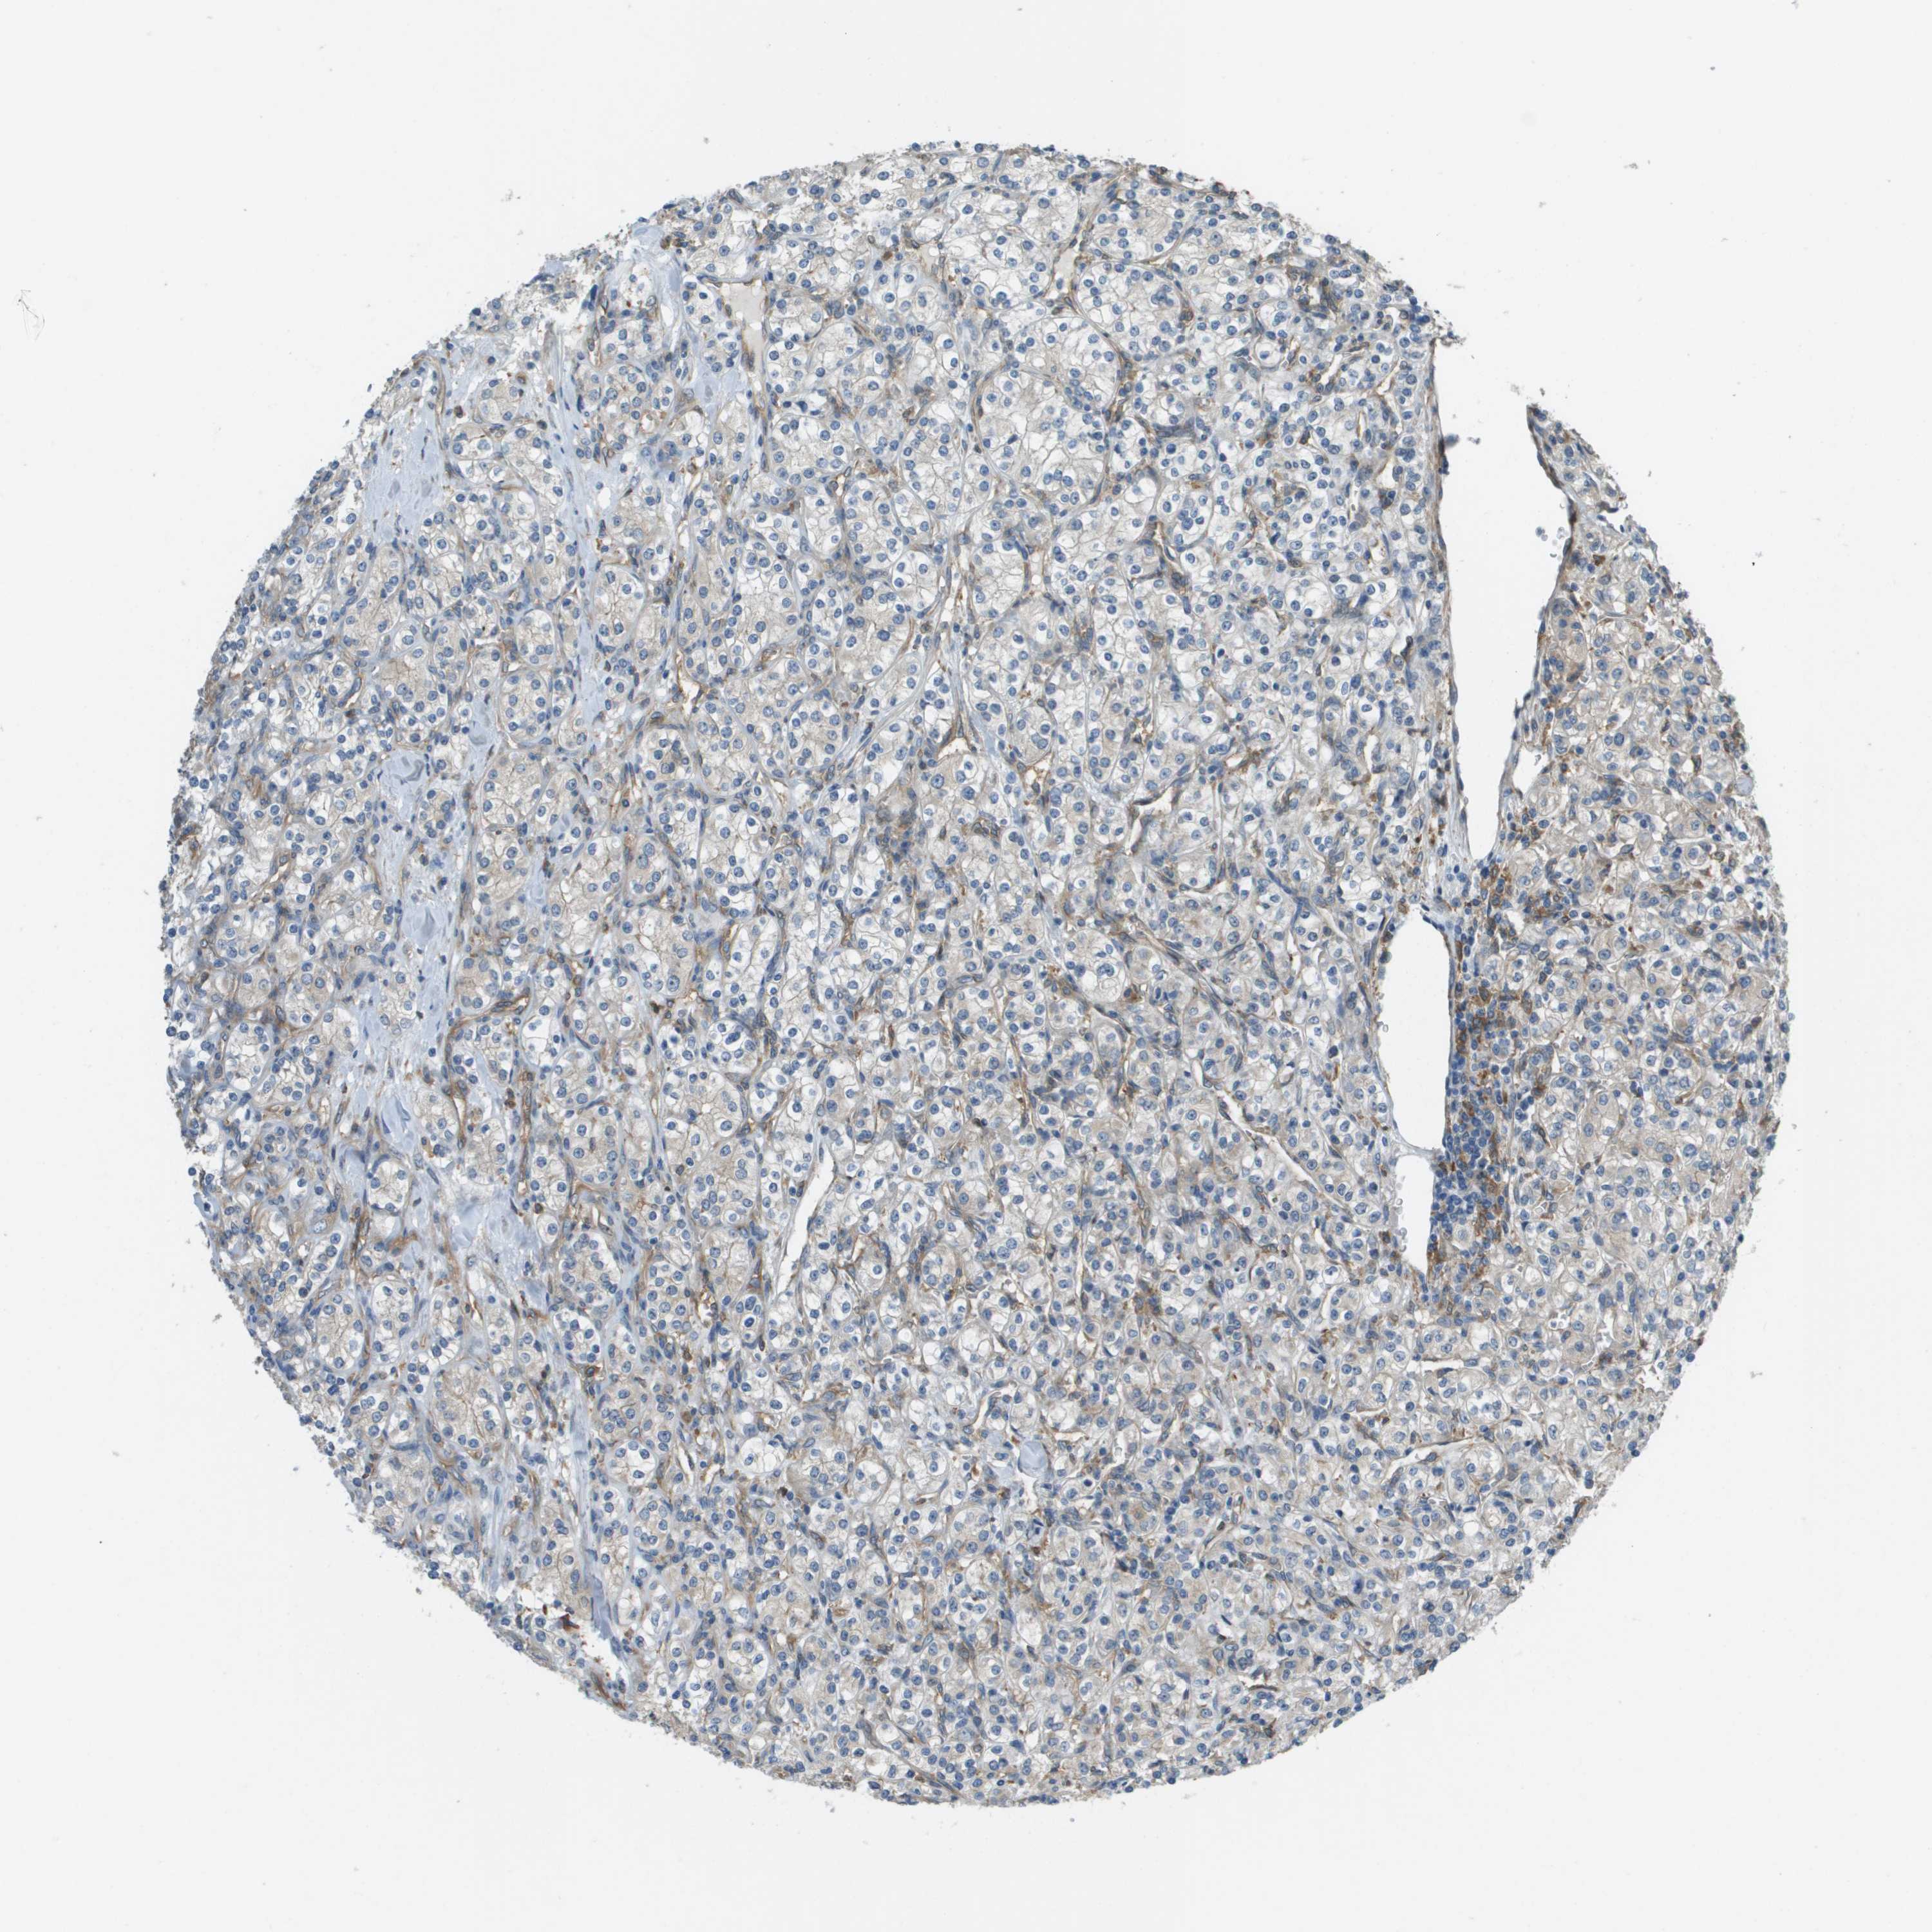

KIDNEY RENAL CLEAR CELL CARCINOMA (TCGA) - Interactive survival scatter ploti

The Survival Scatter plot shows the clinical status (i.e. dead or alive) for all individuals in the patient cohort, based on the same data that underlies the corresponding Kaplan-Meier plots. Patients that are alive at last time for follow-up are shown in blue and patients who have died during the study are shown in red.

The x-axis shows the expression levels (FPKM) of the investigated gene in the tumor tissue at the time of diagnosis. The y-axis shows the follow-up time after diagnosis (years). Both axes are complimented with kernel density curves demonstrating the data density over the axes. The top density plot shows the expression levels (FPKM) distribution among dead (red) and alive patients (blue). The right density plot shows the data density of the survived years of dead patients with high and low expression levels respectively, stratified using the cutoff indicated by the vertical dashed line through the Survival Scatter plot. This cutoff is automatically defined based on the FPKM cutoff that minimizes the p-score. The cutoff can be changed by dragging the vertical line or by entering a cutoff value in the square labeled "Current cut-off".

Under the Survival Scatter plot the p-score landscape (black curve; left axis) is shown together with dead median separation (red curve; right axis). Dead median separation is the difference in median mRNA expression between patients who have died with high and low expression, respectively. It is calculated as follows: median FPKM expression of dead patients with high expression - median FPKM expression of dead patients with low expression. This is intended to aid the user in visually exploring custom cutoffs and the associated p-scores and dead median separation.

Individual patient data is displayed and can be filtered by clicking on one or more of the category buttons on the top of the page. Categories describing expression level and patient information include: high, low, alive, dead, female, male and tumor stages. The scale of the x-axis can be toggled between linear and log-scale by clicking on the "x log" button. Mouse-over function shows TCGA ID, patient information and mRNA expression (FPKM) for each patient.

& Survival analysisi

Kaplan-Meier plots summarize results from analysis of correlation between mRNA expression level and patient survival. Patients were divided based on level of expression into one of the two groups "low" (under cut off) or "high" (over cut off). X-axis shows time for survival (years) and y-axis shows the probability of survival, where 1.0 corresponds to 100 percent.

CORO1B is not prognostic in Kidney Renal Clear Cell Carcinoma (TCGA)

Best expression cut offi

Based on the FPKM value of each gene, patients were classified into two groups and association between prognosis (survival) and gene expression (FPKM) was examined. The best expression cut-off refers the FPKM value that yields maximal difference with regard to survival between the two groups at the lowest log-rank P-value. Best expression cut-off was selected based on survival analysis .

When clicking on this number, the vertical dashed line indicating cut-off, the interactive survival plot, and the Kaplan-Meier curve will be adjusted to show results based on the best expression cut-off.

: 52.2

P scorei

Log-rank P value for Kaplan-Meier plot showing results from analysis of correlation between mRNA expression level and patient survival.

N/A

TCGA RNA samplesi

RNA-seq data is reported as average FPKM (number Fragments Per Kilobase of exon per Million reads), generated by the The Cancer Genome Atlas (TCGA) .

Normal distribution across the dataset is visualized with box plots, shown as median and 25th and 75th percentiles. Points are displayed as outliers if they are above or below 1.5 times the interquartile range. FPKM values of the individual samples are presented next to the box plot.

Average pTPM 56.6

Number of samples 521